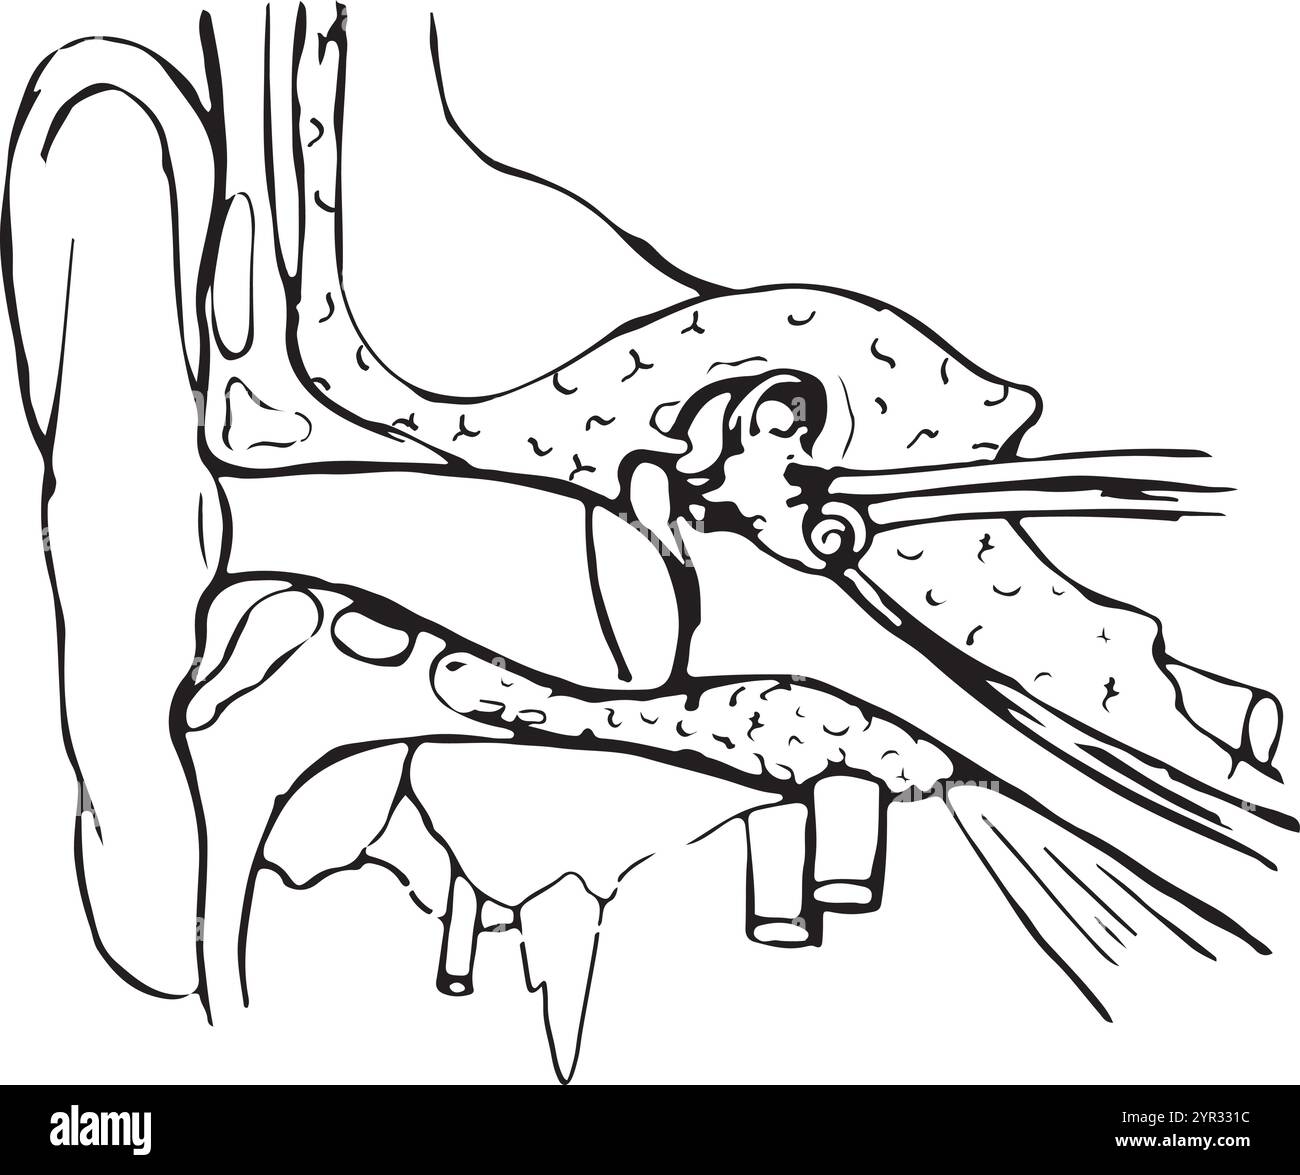

Schéma illustrant l'anatomie de l'oreille externe et interne, dessin de ligne vintage ou illustration de gravure. Illustration de Vecteurhttps://www.alamyimages.fr/image-license-details/?v=1https://www.alamyimages.fr/schema-illustrant-l-anatomie-de-l-oreille-externe-et-interne-dessin-de-ligne-vintage-ou-illustration-de-gravure-image359334904.html

Schéma illustrant l'anatomie de l'oreille externe et interne, dessin de ligne vintage ou illustration de gravure. Illustration de Vecteurhttps://www.alamyimages.fr/image-license-details/?v=1https://www.alamyimages.fr/schema-illustrant-l-anatomie-de-l-oreille-externe-et-interne-dessin-de-ligne-vintage-ou-illustration-de-gravure-image359334904.htmlRF2BTH39C–Schéma illustrant l'anatomie de l'oreille externe et interne, dessin de ligne vintage ou illustration de gravure.

Dessin au trait de la structure de l'oreille humaine. Illustration de Vecteurhttps://www.alamyimages.fr/image-license-details/?v=1https://www.alamyimages.fr/dessin-au-trait-de-la-structure-de-l-oreille-humaine-image633778584.html

Dessin au trait de la structure de l'oreille humaine. Illustration de Vecteurhttps://www.alamyimages.fr/image-license-details/?v=1https://www.alamyimages.fr/dessin-au-trait-de-la-structure-de-l-oreille-humaine-image633778584.htmlRF2YR331C–Dessin au trait de la structure de l'oreille humaine.